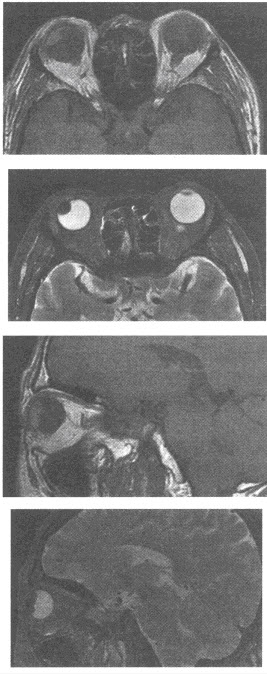

女性,51岁。右眼视力模糊,近日来加重。行MRI检查图像如下,最可能的诊断为()

A:脉络膜血管瘤

B:黑色素瘤

C:转移瘤

D:渗出性视网膜炎

E:视网膜剥离